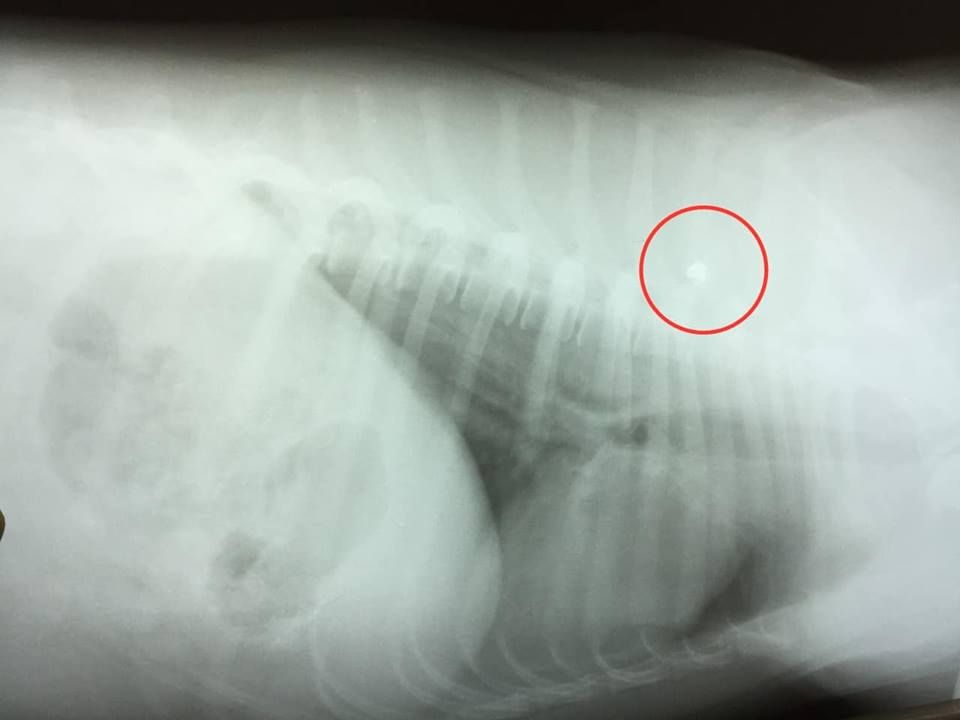

Когда ветеринары принялись осматривать раны собаки – ужаснулись. Кроме того, что Мячика сбила машина, в него еще и стреляли. Малоберцовую кость спасти невозможно, большая ее часть отломалась. Пуля чудом не задела спинной мозг. Есть глубокая рваная рана. При этом собака выжила. Но ей предстоит перенести сложную операцию. Волонтеры обращаются ко всем неравнодушным с просьбой помочь псу.

«Стоимость операции — 2 200 гривен. Мячик очень маленький пес, на фото он конечно намного больше выглядит. Такая кроха чудом выжила, причем 2 раза», — говорится в сообщении от волонтеров.